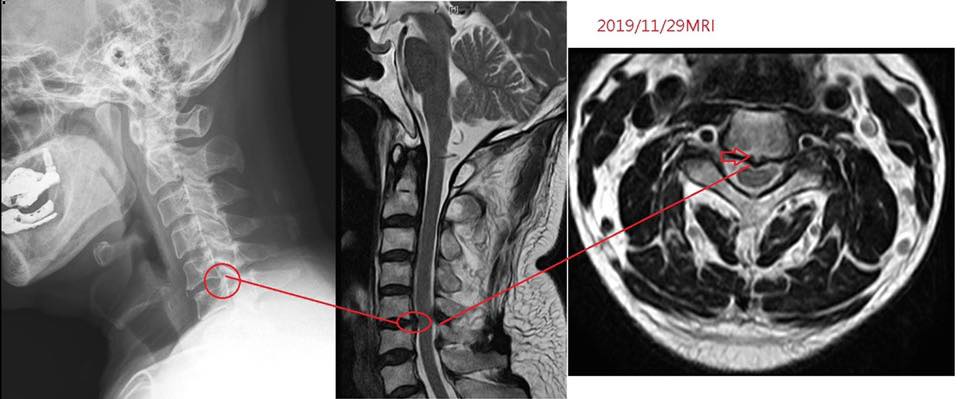

Cervical Spine Treatment Cases 頸椎治療案例 #疼痛三年頸椎病患者親手寫下治療紀錄 #交感神經型頸椎病 #症狀錯綜複雜 2020.10.02 #困擾四年多胸悶手麻頭暈醫案 #一切原因居然是頸椎出問題 #交感神經型頸椎病症狀錯綜... 2020.09.11 #交感神經型頸椎病引起的耳鳴 #耳鳴將近八個月終於得到重大改善 #曾經耳鳴到無法睡覺... 2020.08.22 #感謝板橋蘇先生熱情見證 #神經根型頸椎病卡壓 #曾痛痛到左手無法騎單車撥桿 #麻脹刺... 2020.08.04 #後縱韌帶鈣化引起椎管狹窄 #痛到完全無法睡覺長達半年以上 #原本已經準備開刀最後逆... 2020.07.16 #牽一頸而動全身的特殊醫案 #兩分鐘瞭解交感神經型頸椎病 #絕望的黑暗人生看到一絲希... 2020.07.03 #長達七年的頸椎疼痛是怎麼回事 #神經根型頸椎病 #低頭族跟家庭主婦辛苦了 #逆轉勝醫... 2020.07.01 #頸椎整合中醫微創療法 #感謝新竹黃大哥熱情見證 #逆轉勝成真醫案 2020.06.25 #頸椎病手術後也要要好好保健 #毛巾操很重要再度上場 #感謝某大醫學中心主任見證 2020.06.24 #這些症狀很可能都是頸椎出問題 #患者看七種不同科別醫師找不出原因 #交感神經型頸椎... 2020.06.09 #消失的頸椎曲線能夠回來嗎? #核磁共振前後對比椎管容積打開 #脊椎整合中醫微創療法❤... 2020.06.05 #感謝新竹薛大哥熱情見證 #頸椎整合中醫微創療法 治療:4/21~5/30(八次) 效果顯著... 2020.05.30 從宜蘭來的游小姐患者熱情見證 頸椎整合中醫微創療法 逆。轉。成。真。 2020.05.29 #脊髓型頸椎病案例 2020.05.26 #感謝新北市黃小姐熱情見證 #疼痛時間超過一年 #晨起麻痛到不行的日子長達半年以上 #... 2020.05.16 ← 上一頁 5 6 7 8 9 下一頁 →